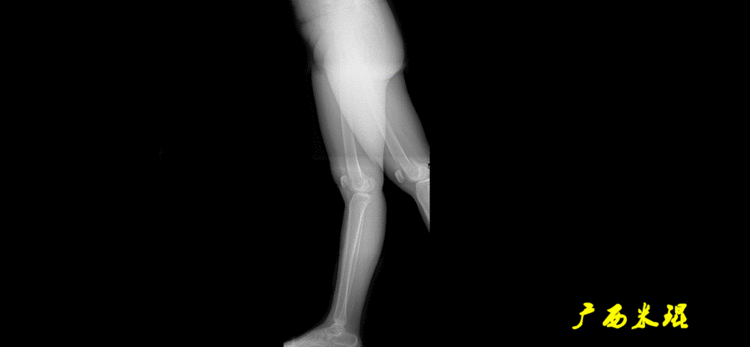

解剖胫骨近端外侧角(也叫aMPTA):胫骨干上段轴线与胫骨平台切线(关节线)在膝关节外侧所形成的夹角,常称为胫骨角,正常为87°±3°。大多数膝内翻患者的畸形发生于胫骨上端,表现为胫骨角大于90°。严重的膝内翻畸形发生在整个下肢,股骨干及胫骨干都有可能形成向内弯曲的弧形。

1、判定有无畸形下肢的畸形定义为生理轴线的偏移。关节角和轴线在冠状面、矢状面和横断面上可发生病理改变,并引起整个下肢的对线异常。

最常见的下肢畸形发生于冠状面,即膝内外翻畸形,冠状面的对线异常通过应用“对线异常检验”进行分析,机械轴的偏移(MAD)表现为对线异常。

膝内翻是指下肢力线通过膝关节中心点内侧,距中点2mm以上,偏内超过15mm为显著膝内翻。膝外翻是指下肢力线通过膝关节中心点外侧,距中点2mm以上,偏外超过10mm为显著膝外翻。